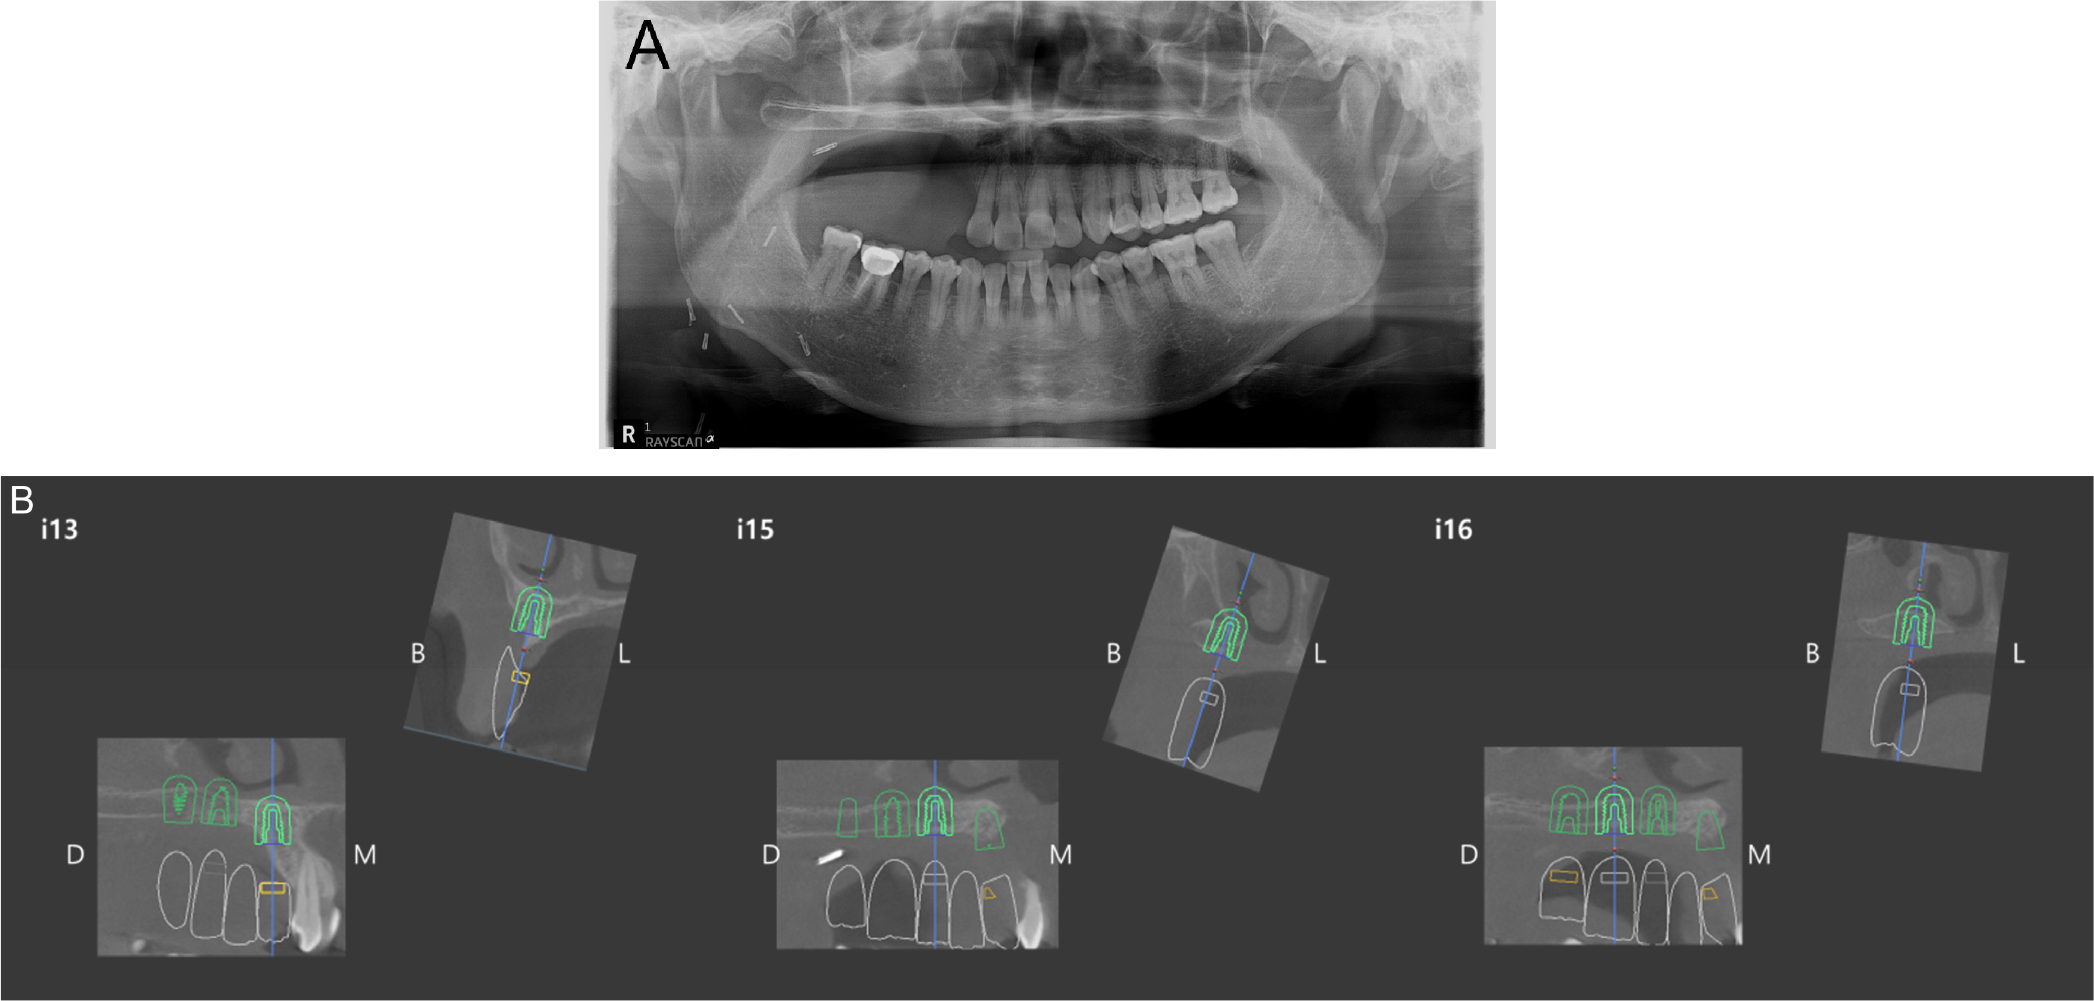

After confirming the absence of recurrence, a dental implant surgery was performed two years after the tumor resection surgery. The position of the implant was determined during consultation with the Department of Prosthetics, and a surgical stent was fabricated for the implant placement (Fig. 6). Three implants (#13i and #15i: IS III 4.5 × 8.5 mm, #16i: IS III 5.0 × 8.5 mm; Neobiotech, Seoul, Korea) were placed under local anesthesia. The bone width and height were adequately maintained during the implant placement. Among the three implants, #16i and #17i had excellent initial stability (>30 N); however, #13i did not show initial fixation. Therefore, a second-stage surgery was performed.

Dental implants were placed two years after the oral cancer surgery. Prior to the dental implant surgery, dental cone-beam CT was performed to evaluate the remaining bone status and fabricate the surgical stent, which revealed that the height of the remaining bone was 6–8 mm. Dental implants (8.5 mm height) were placed with a prefabricated surgical stent using bicortical anchorage to ensure a greater amount of bone-implant interface.